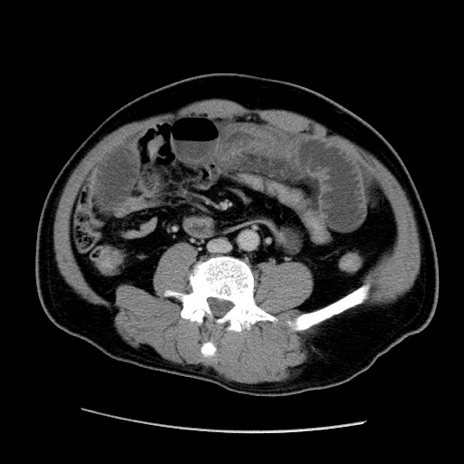

症例22(横断像)

【症例】50歳代男性

【主訴】腹痛

【現病歴】AVMからの被殻出血のため回復期リハ病棟入院中。 本日午後3時頃急に下腹部痛が出現した。

【既往歴】AVM、被殻出血、虫垂炎、高血圧

【身体所見】意識晴明、左半身不全麻痺、会話の理解は良好、36.5°C、腹部:膨隆、全体に板状硬、下腹部正中に圧痛点あり、反跳痛-、筋性防御不明、右下腹部にope scar

【データ】WBC 9400、CRP 0.06